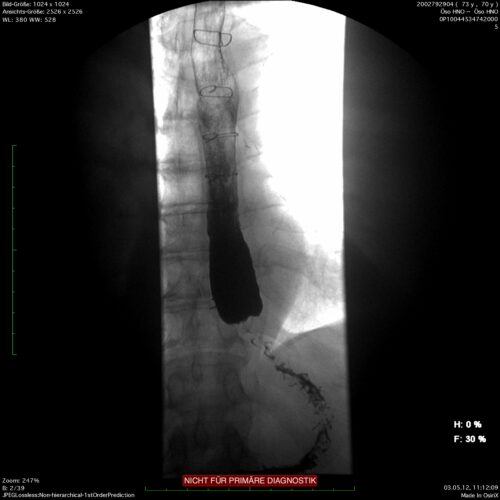

Der erhöhte Tonus des unteren Ösophagussphinkters und dessen inkomplette Erschlaffung führen in der Folge zu einer Dilatation des tubulären Ösophagus. Dies gibt der Achalasie das charakteristische Aussehen in der Röntgen-Kontrastmitteldarstellung. Von der primär idiopathischen Achalasie sind sekundäre Formen oder die Pseudoachalasie abzugrenzen, bei der z.B. ein Kardia- oder Ösophaguskarzinom für die Dysphagie und die morphologischen Veränderungen der Speiseröhre verantwortlich ist. Der Ausschluss einer malignen Grunderkrankung gehört immer zur Differentialdiagnose einer Dysphagie, neben der obligaten Endoskopie kann dies auch eine CT notwendig machen.

Das klassische Bild einer Sektglas- oder Sanduhrform zeigt sich in der Durchleuchtung bei der Kontrastmittelschluckuntersuchung. Hier kann auch das Ausmaß der Dilatation gut beurteilt werden. Spiegelbildungen im Ösophagus weisen auf eine Stase hin. Die Endoskopie hilft, eine sekundäre Ursache, wie z.B. ein Karzinom, auszuschließen.